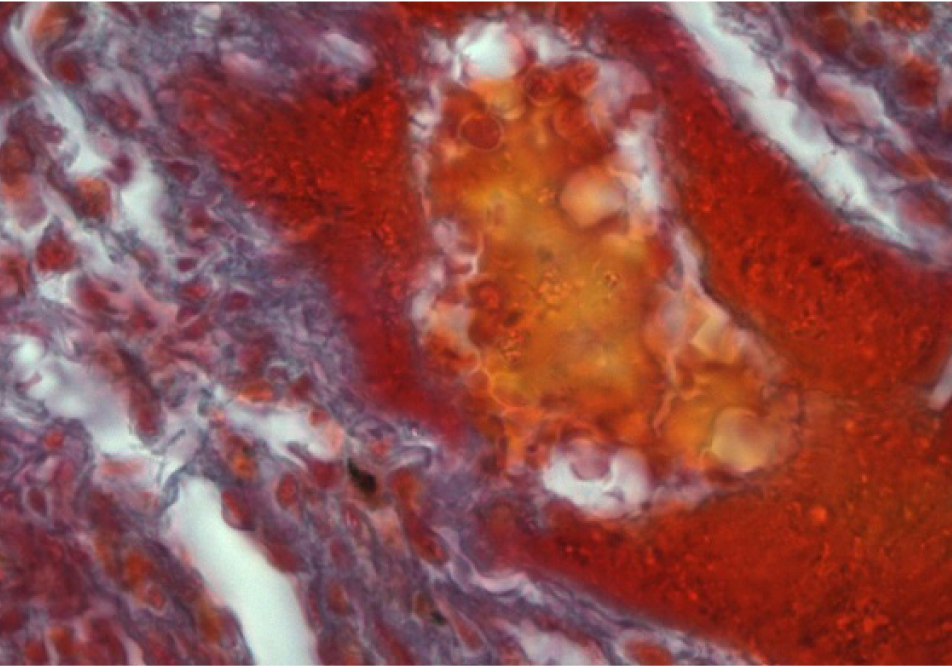

Наблюдается активизация фибробластов, окруженных пучками коллагеновых волокон (рис. 3, 4).

Рис. 3. Образование коллагеновых волокон в интерстици- альной ткани легкого. Окраска по Маллори. Ок. 10. Об. 100. Иммерсия

Рис. 4. Образование коллагеновых волокон в стенке сосуда. Окраска по Массону. Ок. 10. Об. 100. Иммерсия

Крупные скопления многоядерных макрофагов в межальвеолярных перегородках легочной ткани свидетельствуют о выраженной макрофагальной реакции. Наличие фибробластов, активно продуцирующих коллагеновые волокна, подтверждает фиброгенные свойства фталата свинца. Присутствие эозинофилов в полиморфноклеточных инфильтратах указывает на способность фталата свинца вызывать сенсибилизацию организма. Все вышеперечисленное является доказательством развития хронических воспалительных процессов.